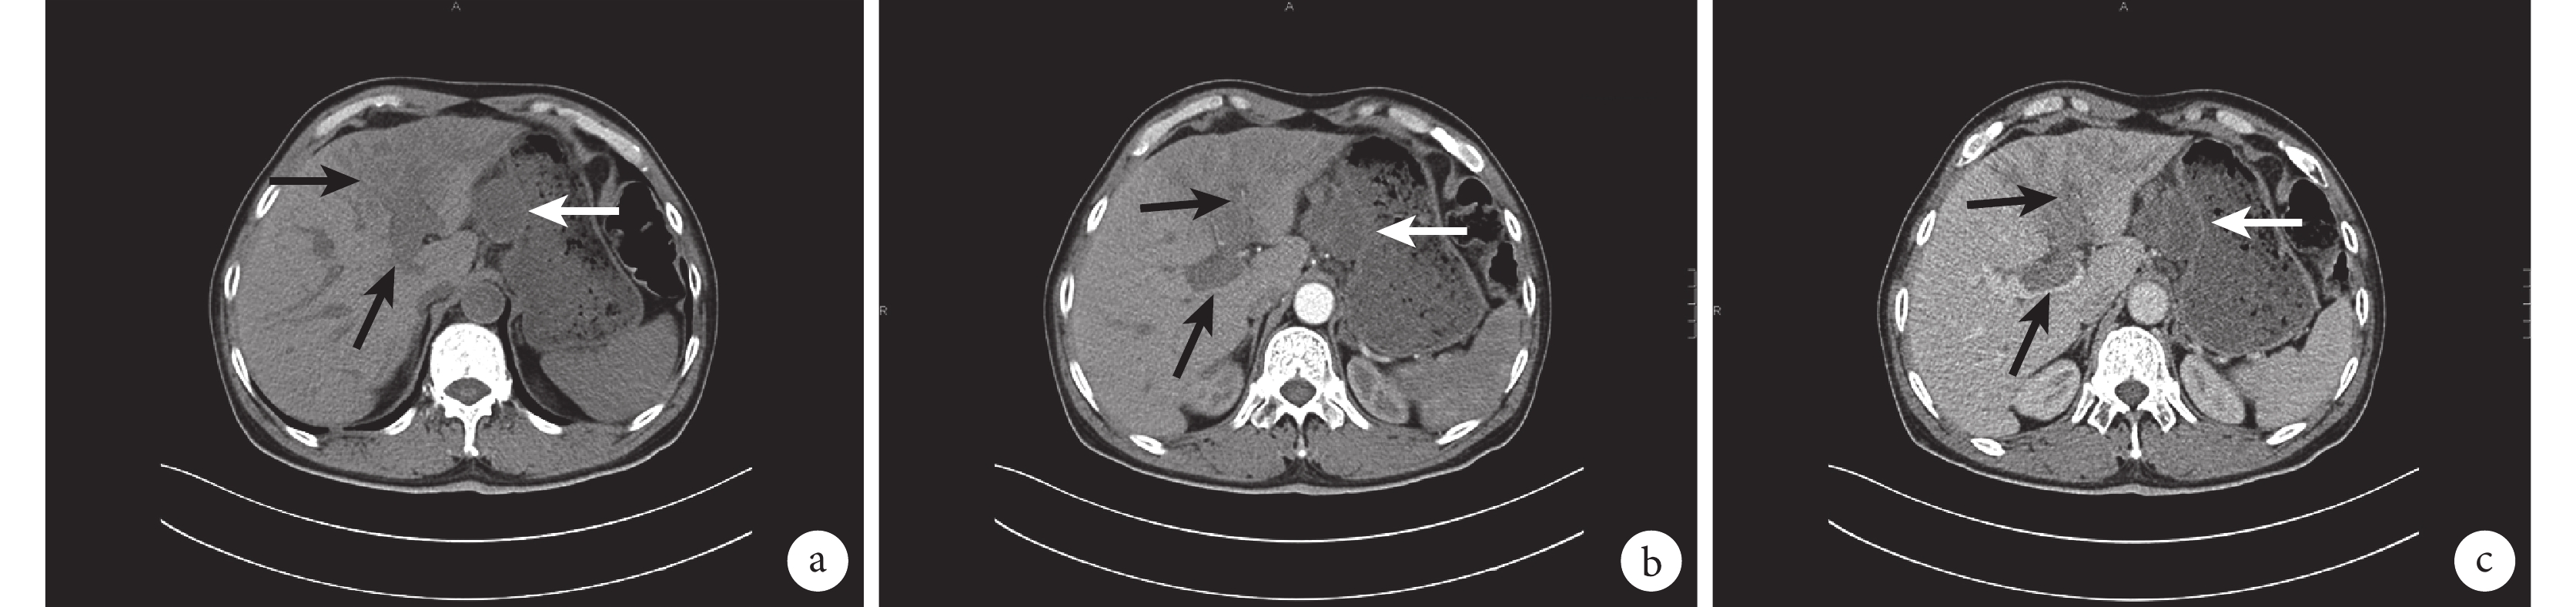

肝臟增強 CT 檢查(圖 1)示:肝左葉一稍低密度片團影,增強掃描呈輕度不均勻強化,并見病灶由肝動脈分支供血,肝內膽管明顯擴張,以肝左葉為著,局部病變與胃竇壁分界欠清;肝實質內少許不規則片狀稍低密度影,輕度強化;肝門區及肝胃韌帶旁見明顯腫大淋巴結,較大者約 3.9 cm×3.2 cm,并見液化壞死;門靜脈主干見一約 3.5 cm×1.3 cm大的低密度影。據以上考慮肝左葉腫瘤伴周圍淋巴結轉移、肝內轉移可能,門靜脈癌栓形成。

a:平掃圖像;b:動脈期圖像;c:靜脈期圖像;上黑箭指示肝左葉病灶,下黑箭指示門靜脈,白箭指示肝胃間隙腫物